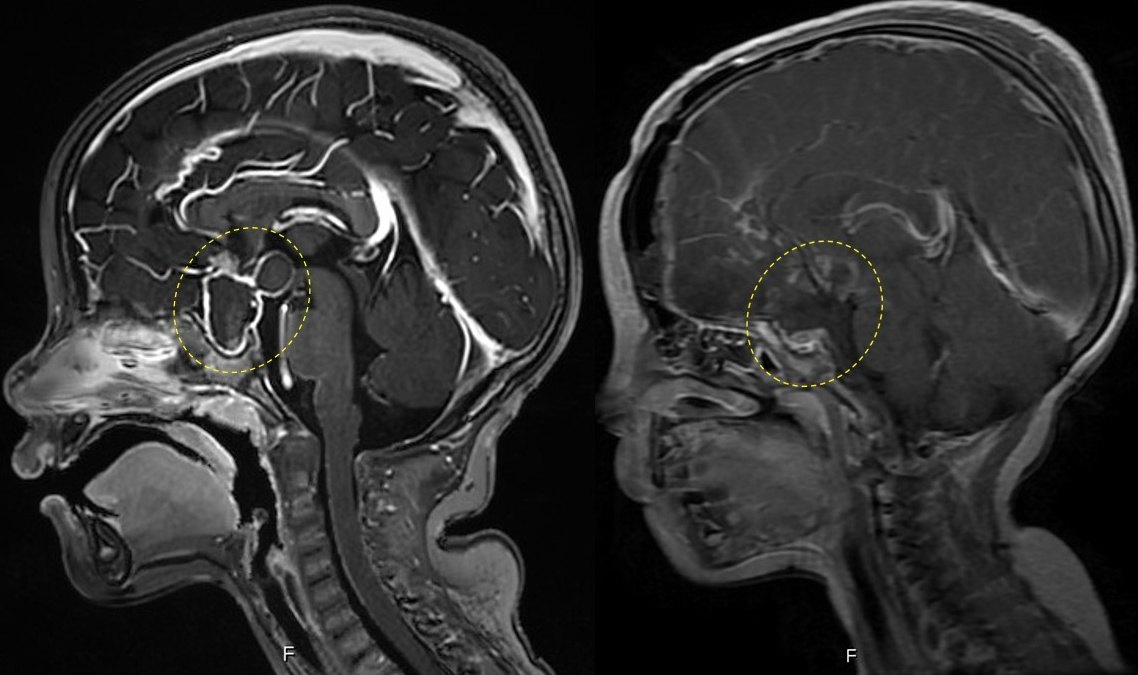

颅咽管瘤的影像诊断 | 影像天地_曹丽珍

图片尺寸960x720

内镜下颅咽管瘤一例

图片尺寸750x524